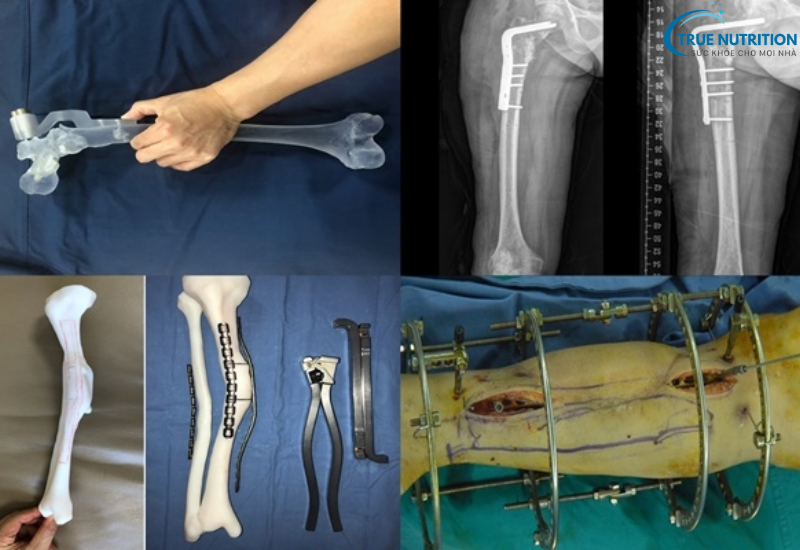

Ổ gãy có nhiều mảnh vụn

Các ổ gãy dạng này không thể liền tự nhiên mà cần sự hỗ trợ từ các dụng cụ y khoa như nẹp vít, đinh nội tủy để đảm bảo ổn định.

- Xử lý ổ gãy: Bác sĩ làm sạch vùng gãy, loại bỏ mô hoại tử, sau đó sử dụng dụng cụ như đinh, nẹp, hoặc vít để cố định ổ gãy.

Biến Chứng Từ Dụng Cụ Kết Hợp Xương

Đối với các trường hợp gãy xương phức tạp, bác sĩ có thể sử dụng các dụng cụ kết hợp như vít, đinh, nẹp hoặc kim loại để cố định xương. Mặc dù các dụng cụ này giúp ổn định xương và giảm thiểu sự lệch lạc trong quá trình hồi phục, nhưng chúng cũng tiềm ẩn một số nguy cơ, chẳng hạn như: